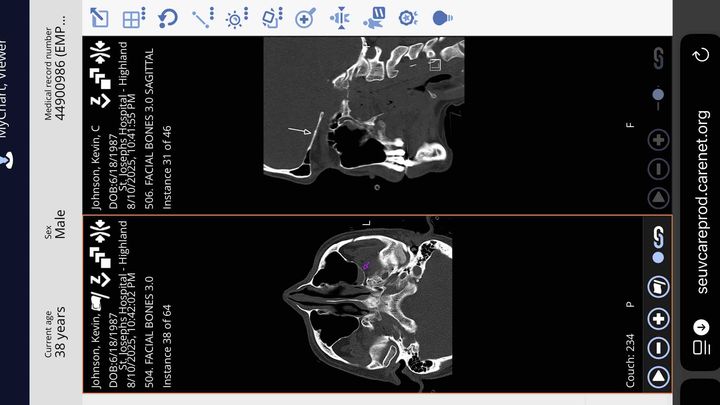

Hi, I’m Kevin Johnson. Not long ago, I was in a serious accident while test-riding my rebuilt e-bike. I don’t remember what happened, but the crash left me with three skull fractures and a brain bleed that could have been life-threatening. The damage to my bike was so severe that doctors believe it may have been caused by a collision with a vehicle, possibly even a hit-and-run. I was airlifted to Barnes Hospital in St. Louis for emergency care, and I’m grateful to be here today and recovering.